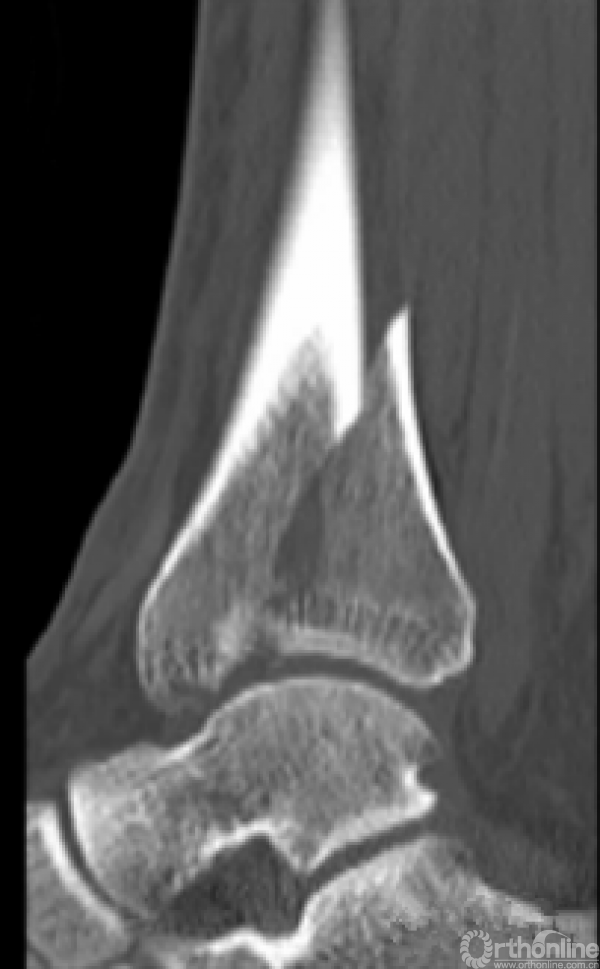

对于以下的骨折你怎么选择入路?

这样的骨折呢?